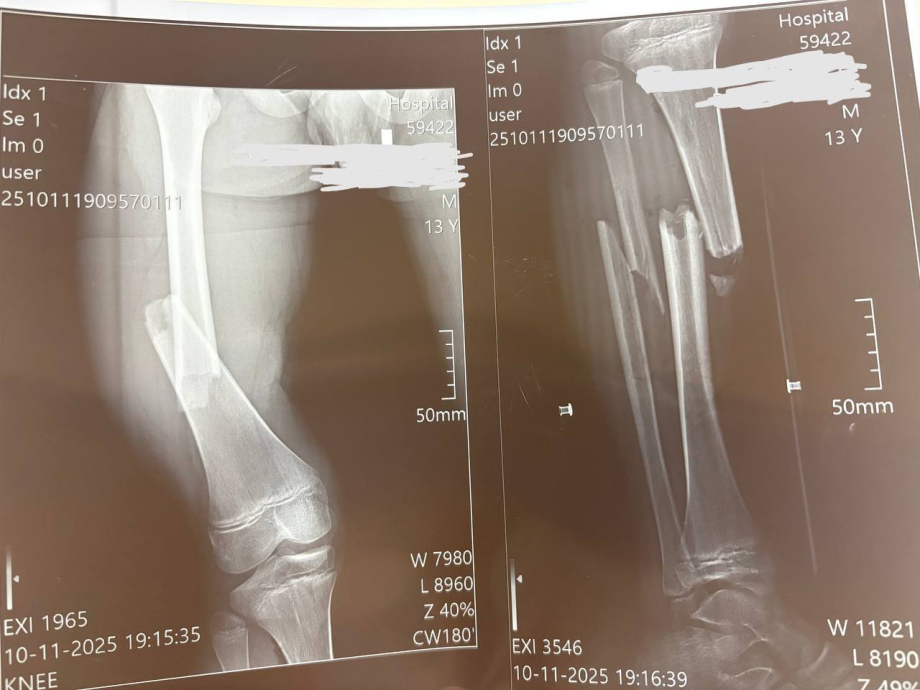

Остеосинтез – це технічний процес, за допомогою якого кістки виводяться в правильне положення і закріплюються за допомогою різних пристроїв. Це можуть бути металеві пластини, гвинти, стержні, або шпильки. Іноді це виглядає як скульптура з металу всередині вашого тіла, але, чесно кажучи, це не зовсім так романтично. Важливе питання, яке варте уваги: коли ж ці прикраси повинні покинути наше тіло?

Коли необхідно видалити остеосинтез?

Основні покази до видалення

- Біль або дискомфорт

- Інфекція

- Обмеження руху

- Підготовка до повторної операції